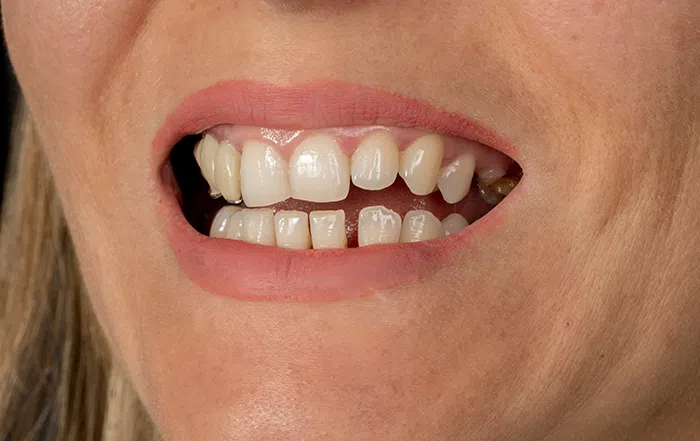

Caz estetica dentară – Coroane de zirconiu și ceramică E-Max

Provocarea acestui caz a fost în obținerea unui plan drept a marginilor incizale a dinților cât și păstrarea unei forme aproximativ identice a vechilor dinți ai pacientului, dar sub o culoare mult mai albă.

Pacientul și-a dorit o culoare Bleach 2, cu mențiunea să păstrăm aproximativ volumul vechilor dinți. Pacientul a beneficiat de corecție gingivala cu laser pentru asimetriile gingivale, tratamente endodontice de canal sub microscop, obturațiile vechi (plombe) schimbate cu materiale de compozit cu particule nanoceramice și coroane de zirconiu ceramică individuale pentru menținerea esteticii.

Termen de finalizare 2 săptămâni de la amprentarea finală.